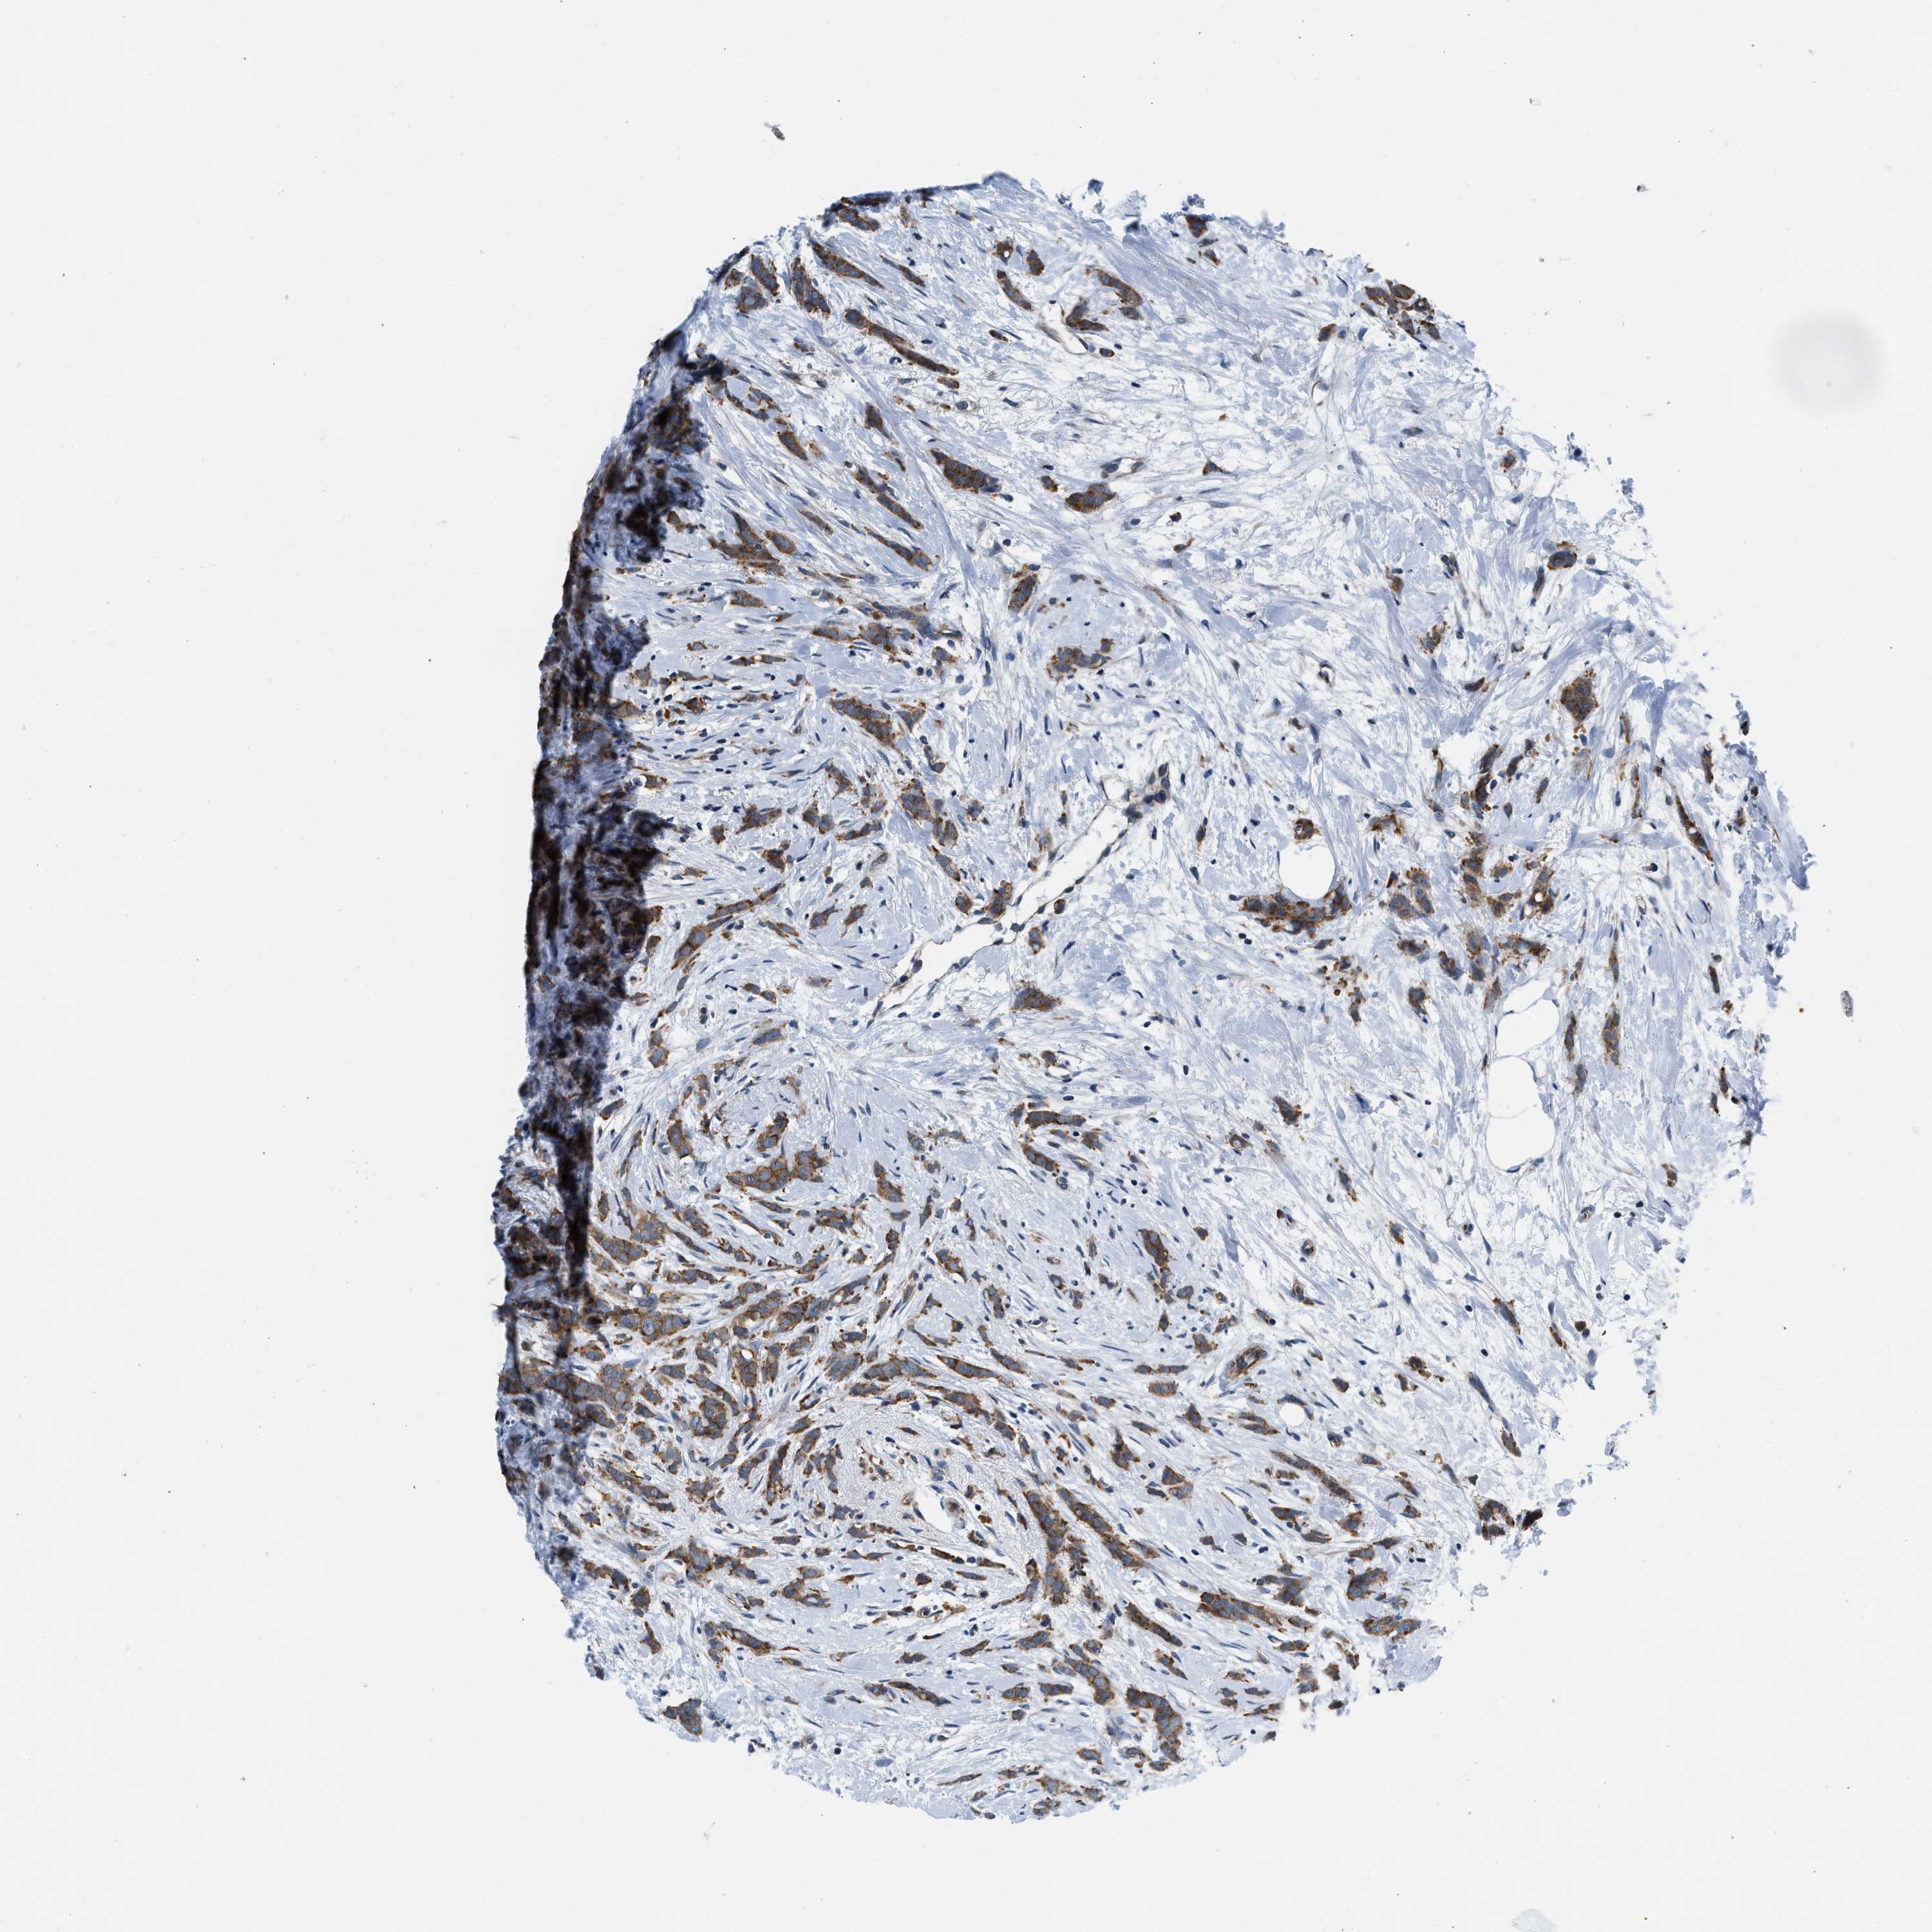

Breast cancer

Human cancer